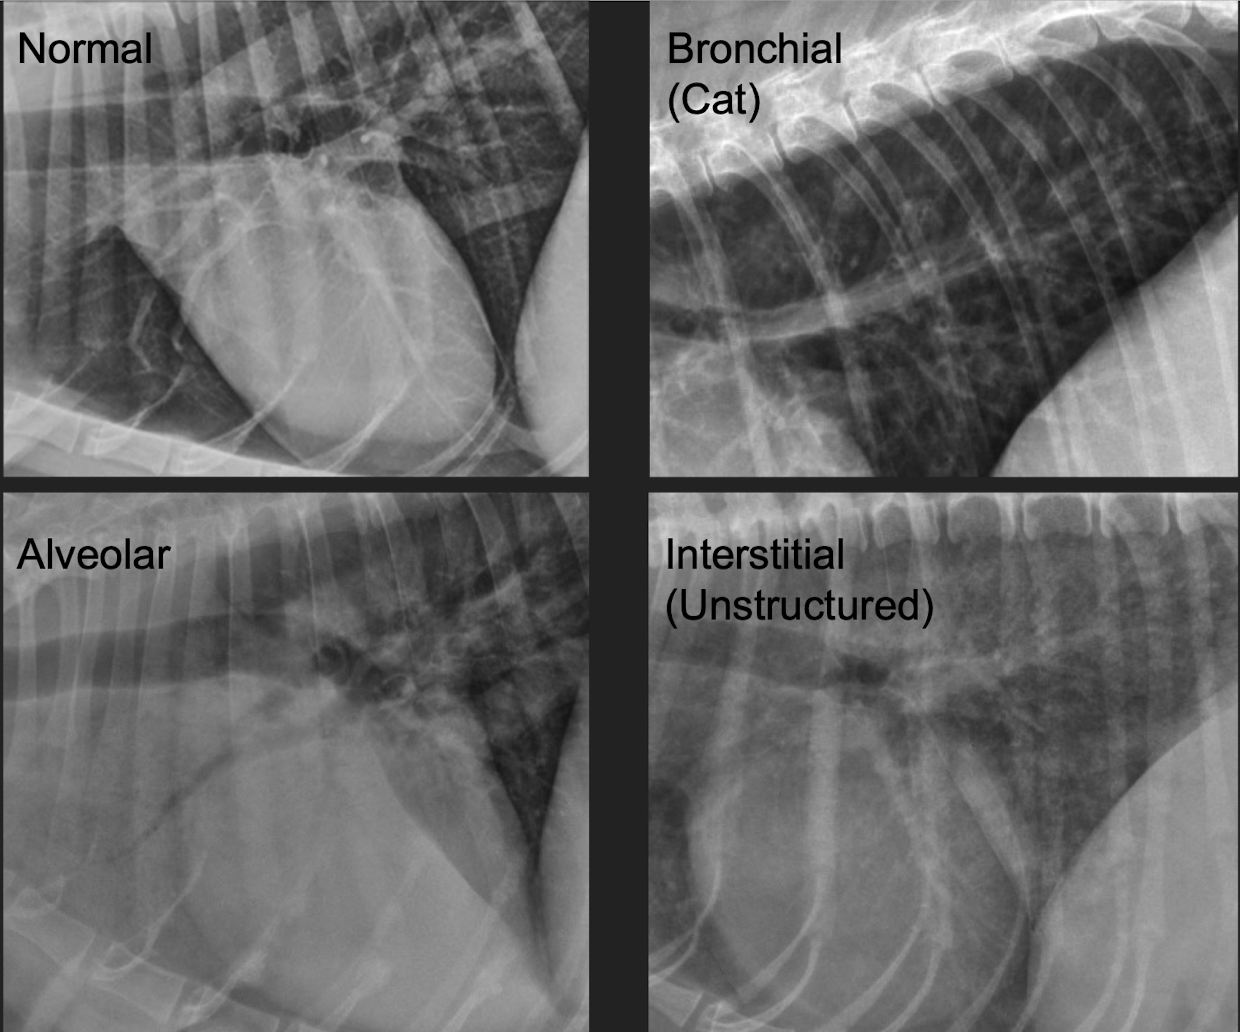

what kind of pattern

unstructured interstitial pattern look like

A

hazy

• generalized increase in pulmonary opacity

• Unsharp outline of pulmonary vessels and airway walls

• Decreased sharpness of the cardiac and diaphragmatic borders (difficult to recognize)

normal- left

interstitial- right